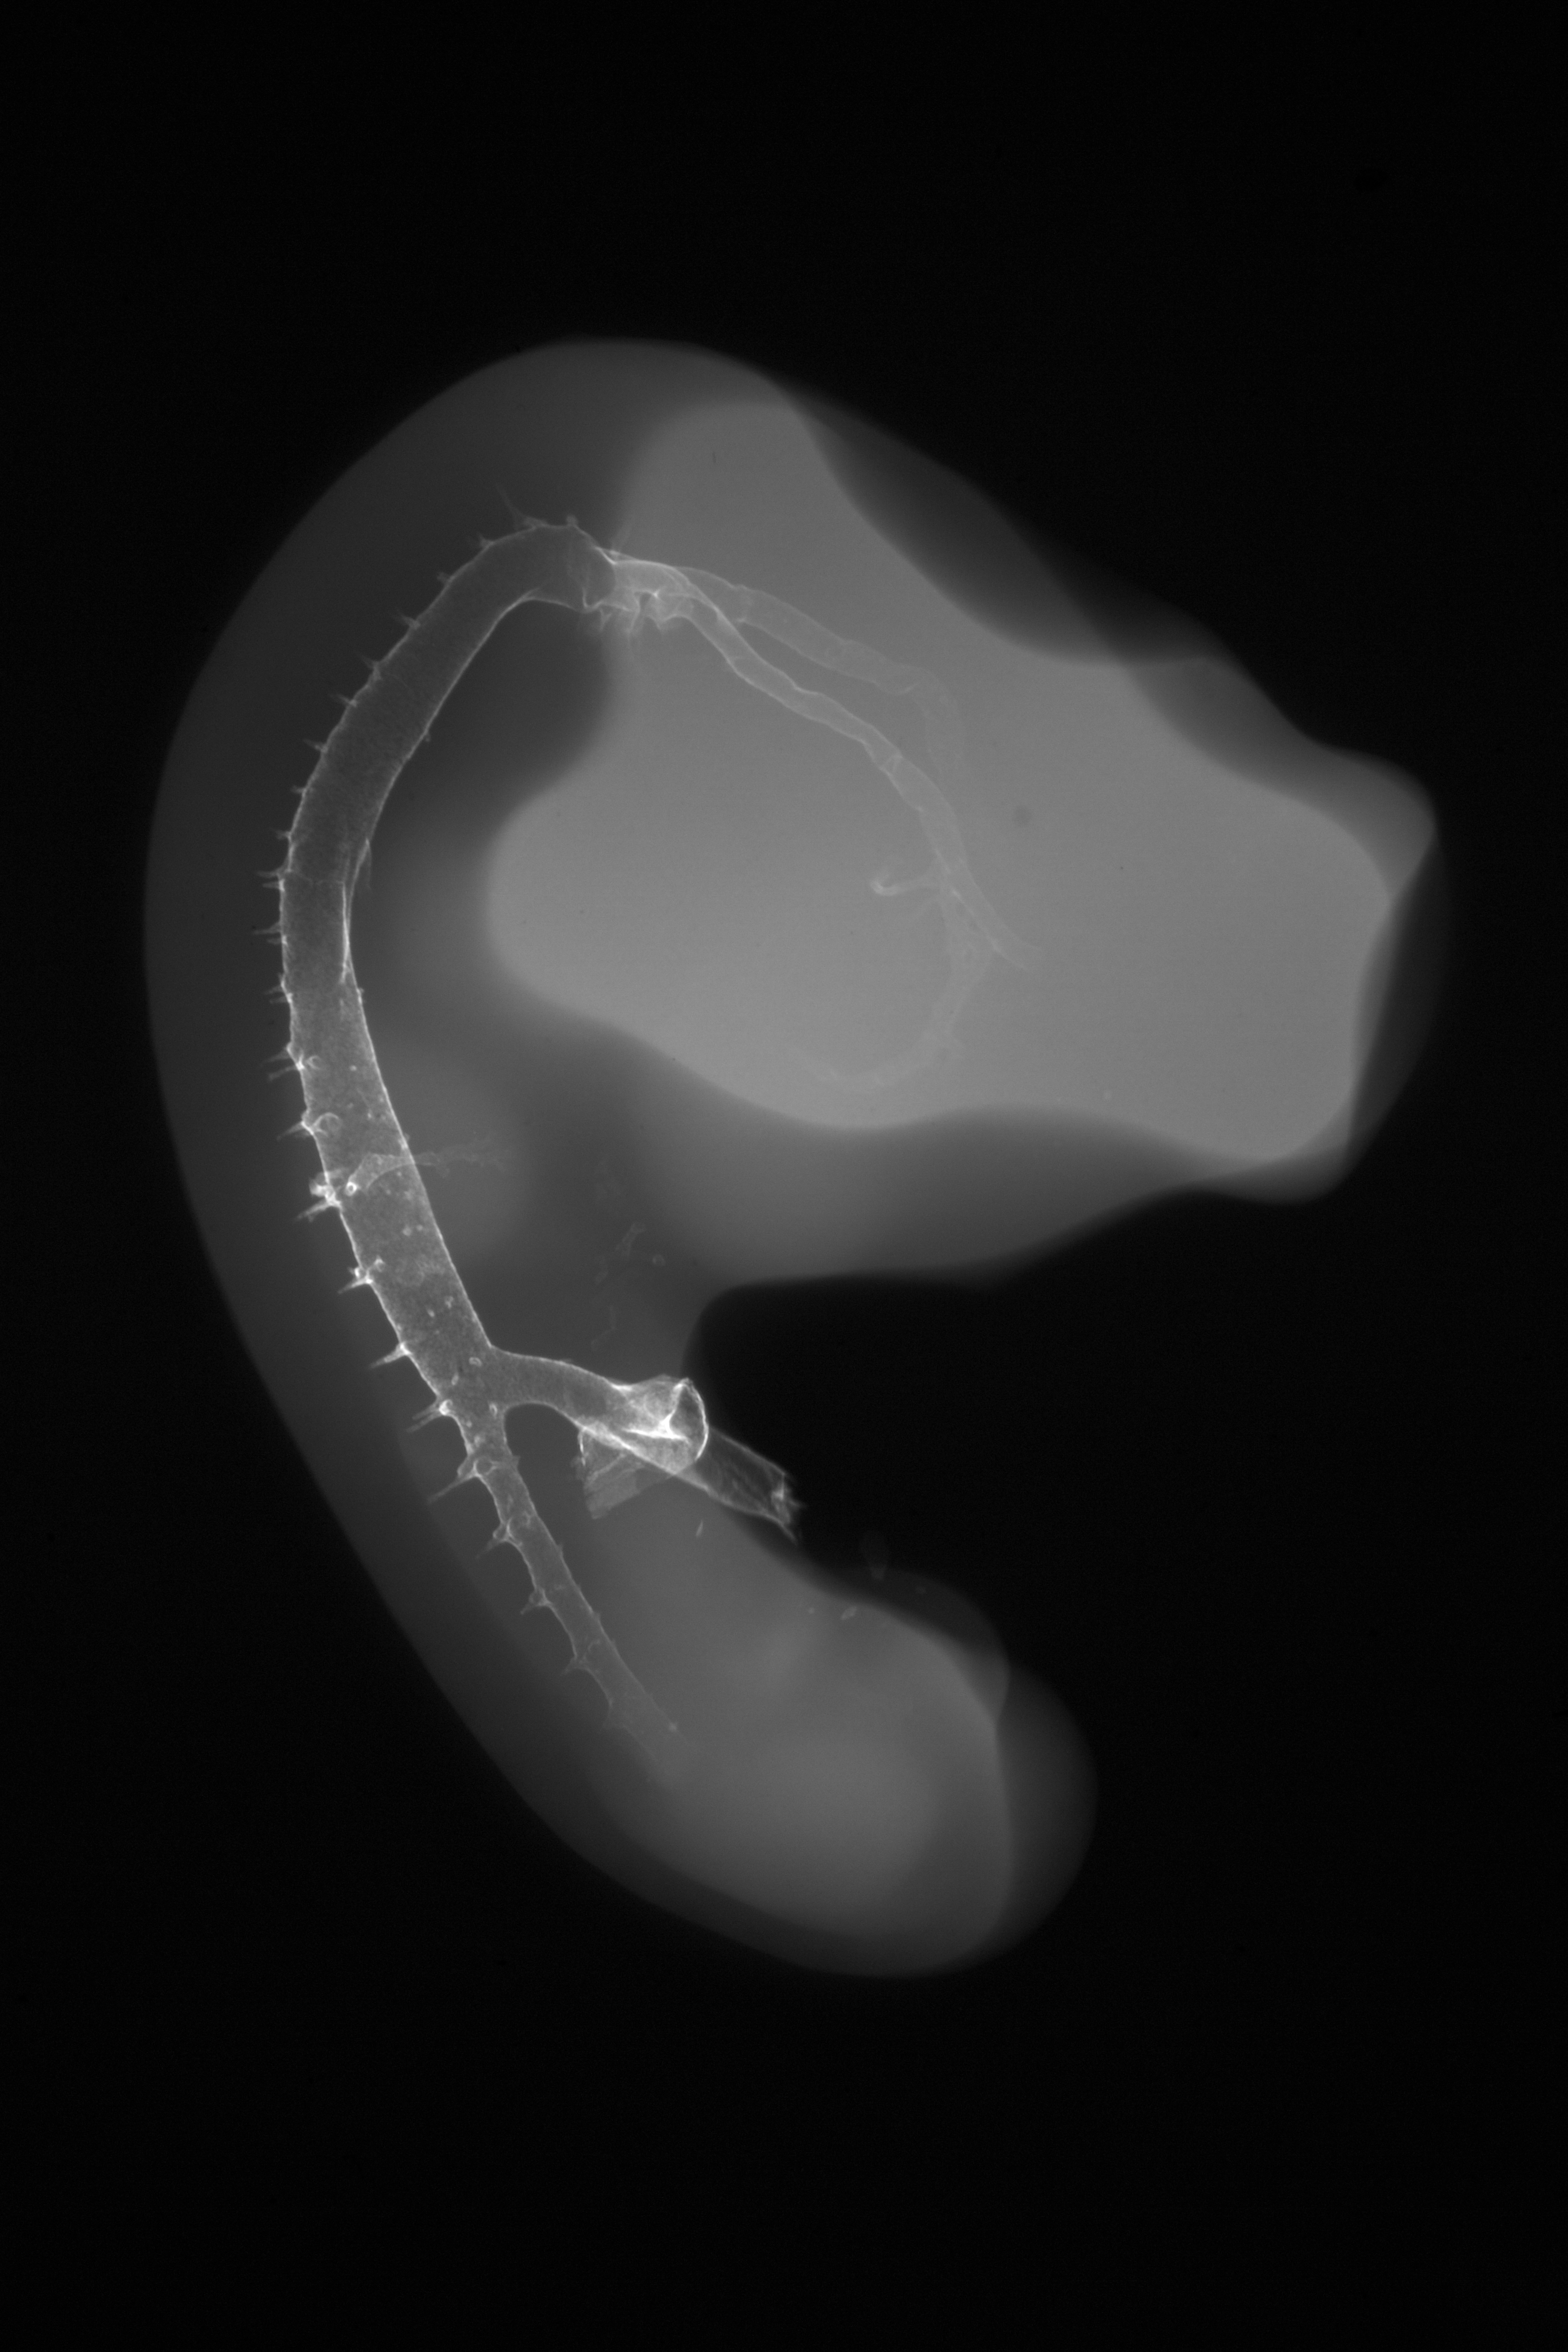

Chick Embryo Microangiography

Hamburger-Hamilton (HH) Stage 23 (approx. 4 days)

X-Ray Micrographs